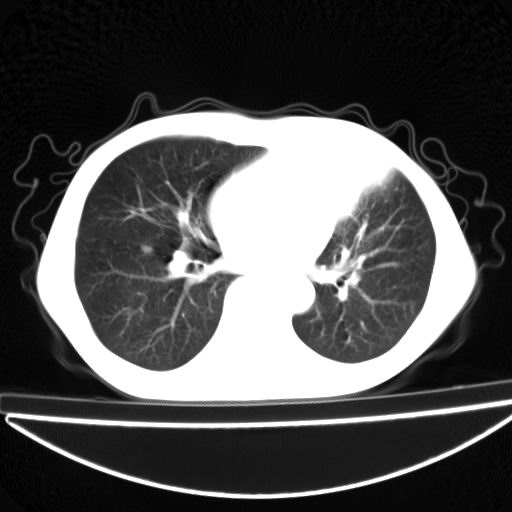

以下是引用杀毒软件在2009-4-28 17:58:00的发言:[br]考虑----左肺慢性肺脓肿形成继发上叶含气不良---抗炎后复查---待排肿瘤所致[br][br][本贴已被 杀毒软件 于 2009-4-28 18:01:26 修改过]